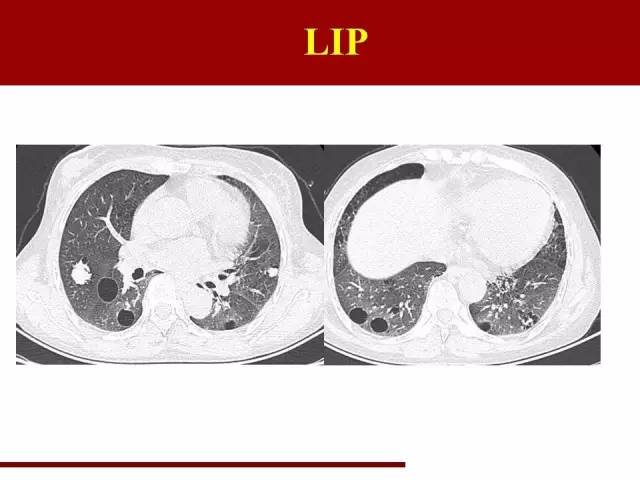

LIP同样是一类疾病的不同阶段,前身是滤泡性细支气管炎

LIP的特点很典型,在幻灯片里已经说过了

袁怀平:

典型的图片,大家一看就能明白